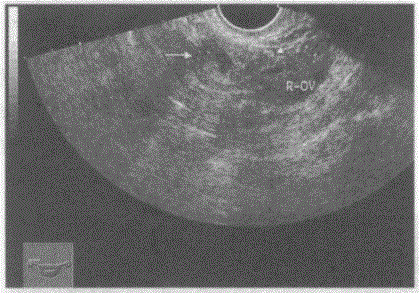

问题 临床资料:女,21岁,自述停经47天,腹痛伴阴道不规则出血2天。 化验检查:尿妊娠试验阳性。 超声综合描述:经阴道扫查子宫形态、大小、回声正常,宫腔内未见胎囊。右附件区见不均质回声,中部为无回声(箭头所示),内见胎芽及胎心搏动。 超声提示:

选项 A.子宫角妊娠 B.右卵巢异位妊娠 C.右卵巢囊肿扭转 D.右输卵管异位妊娠

答案 D